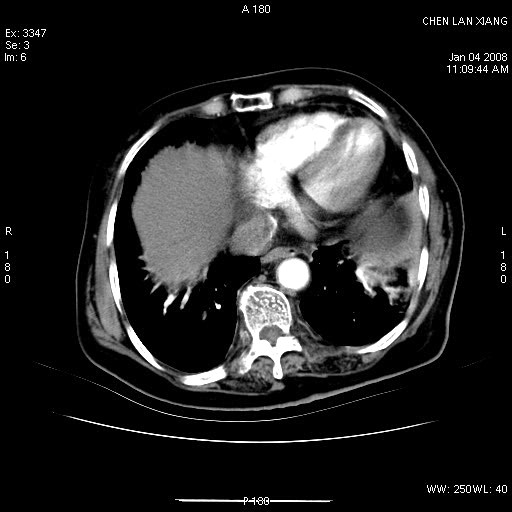

女,76岁,腹痛3-4天,b超示:肝内实性肿物,胆囊强回声,胆总管扩张.

考虑:1、胆总管下端结石伴梗阻性肝内外胆管扩张(肝左叶外侧段肝内胆管多发结石、胆管炎);

2、肿囊癌累及肝,不除外 黄色肉芽肿性胆囊炎。

1 胆总管末端结石伴肝内胆管结石,肝内外胆管扩张。2 胆囊扩大,胆囊壁不规则增厚,内见软组织密度影。考虑:慢性胆囊炎,不除外胆囊癌!

标题: 肝右叶病灶

胆囊癌侵犯肝右叶?

1)胆囊癌伴肝脏转移。2)胆总管下端结石、肝内胆管结石伴肝内外胆管扩张。